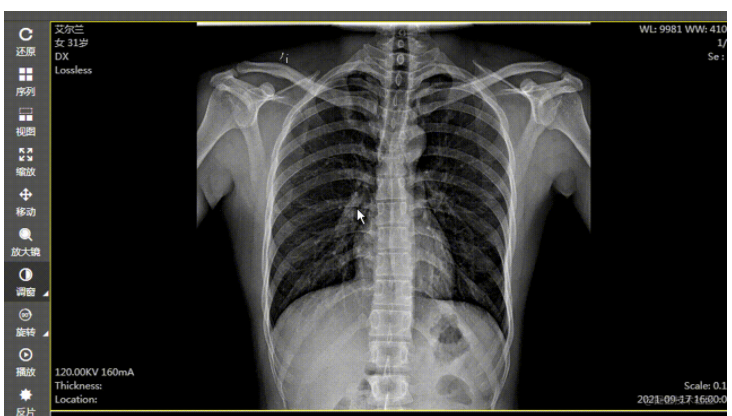

在 web 版阅片器(图像显示工具)的开发工程中发现,在对 dr、dx 这种大图(图像普遍是 2000px 左右宽高的图像,每个像素大小是 16 位或者 32 位的)进行调窗时,浏览器直接卡死,图像显示变化有很大延迟。后来查阅资料,使用 gpujs 来实现调窗时图像的处理,结果:调窗时图像显示变化变得比较线性,性能估计提升 5/6 倍,能满足业务需求。当然,图像的一些高级处理,都是可以用 gpujs 来实现,调窗只是一个点。

使用前效果: